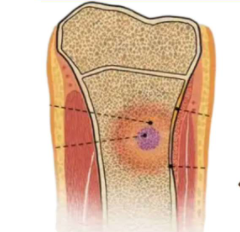

什么是骨髓炎?

不死的癌症

感染性疾病

炎症

是由病原微生物

引起的骨骼系统

感染性病变

包括骨膜、骨密质

骨松质或骨髓组织

的炎症

它并非简单的

“骨头发炎”

而是一种由细菌或

真菌引起的严重

骨骼是活的器官,有丰富的血管和骨髓组织,一旦病原微生物通过某种途径侵入,就会在其中定植,引发炎症反应、化脓、骨质破坏,甚至骨坏死 。